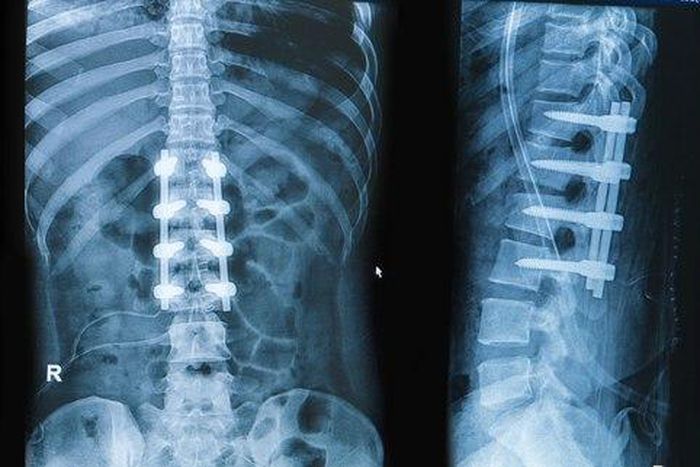

Traditionally, in spinal fusion procedures, bone, metal plates, or screws were used to create bridge between adjacent vertebrae. The ZIP ULTRA is an implant that was developed to substitute the use of screws and metal plates during the spinal fixation. The purpose of the implant is to reduce the load from the thoracolumbar discs. The implant has its own unique locking mechanism, removing the need in screws. The implant is also adjustable, so it can accommodate the needs of various patients.

Innovative and minimally invasive techniques in spinal surgery have a direct impact on the outcome of the procedure, as well as the duration of recovery and the patient comfort during rehabilitation. The ZIP ULTRA fusion system makes spinal fusion a significantly safer procedure with minimal risk of nerve damage. The surgery can be performed under local anaesthesia and be relatively quick with minimal pain.